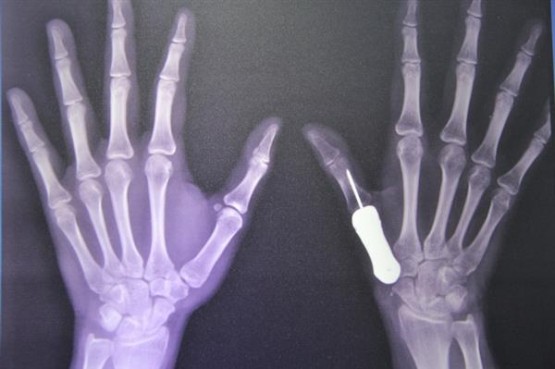

Un equipo de médicos del hospital Phramongkutklao en Bangkok (Tailandia), implantó el hueso de un pulgar impreso en 3D en el dedo de una mujer que tenía una malformación a causa de un tumor. Es la primera vez que se realiza un procedimiento de este tipo.

Tradicionalmente, este tipo de casos se tratan con partecitas de huesos de la cadera o la pierna, pero en esas situaciones, los pacientes no pueden volver usar su dedo con normalidad. Con el implante de titanio impreso en 3D, que es más liviano y fuerte, la paciente de 37 años está utilizando su dedo como la hacía antes de la operación.

El equipo de doctores creó el pulgar a medida escaneando el pulgar izquierdo y sano de la paciente. Aunque el proceso de moldeado llevó sólo una semana, los doctores del hospital pasaron casi dos años investigando y desarrollando el proyecto.

La etapa cirúrgica comenzó en junio de 2015, cuando los doctores quitaron el hueso deteriorado y esperaron hasta septiembre para asegurarse que el tumor no regrese. Luego, los cirujanos implantaron el hueso de titanio al insertarlo en el tendón más cercano en la mano de la paciente.